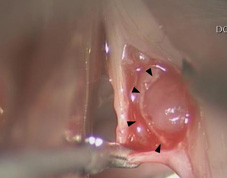

除了傳統聲帶手術,直接將病灶切除的操作方法外,近年來,逐漸發展出聲帶顯微皮瓣手術的新技法,手術中保留聲帶表皮(皮瓣)完整,以精細長柄器械移除深層病灶後(如:圖一、圖二),將皮瓣包覆住聲帶傷口,以恢復聲帶平整的外觀。

圖一、顯微皮瓣手術移除聲帶息肉圖二顯微皮瓣手術移除聲帶囊腫